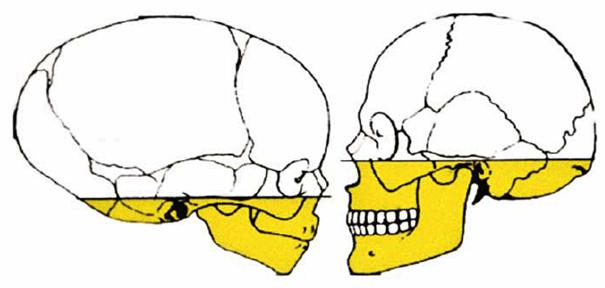

craniofacial growth. At birth, in fact, the splanchnocranium is considerably

hypodeveloped if compared with the neurocranium (Figure 27-12). Furthermore, the mandible is the least

developed of the face's lower third and tends to grow more and for a longer

period of time when compared with the rest of the face. Moreover, a sequence

exists both in the maxilla and in the mandible. This has been defined as a

completion of growth in the three planes of space: first, growth completes in

width, then in length, and then in height. The transversal growth of both bones

(including width of the dental arches) tends to be complete before the pubertal

growth peak and is scarcely influenced by growth variations during adolescence.

Figure 27-12: At birth, the splanchnocranium is considerably hypodeveloped if compared with the neurocranium.